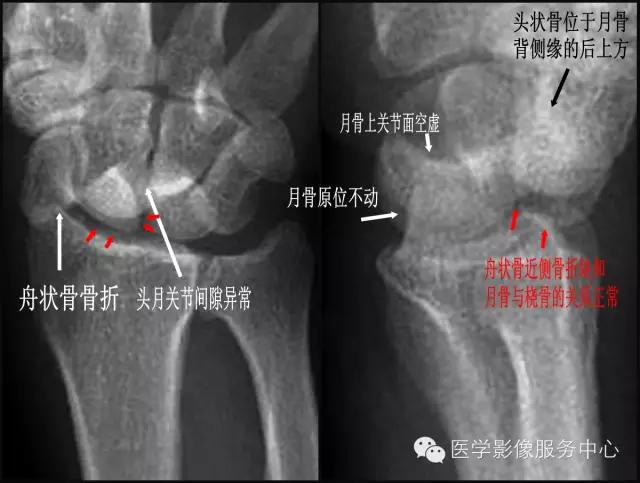

四、经舟状骨月骨周围脱位 【受伤机制】 摔倒时手背伸、尺偏和旋前位着地,发生月骨周围脱位。 【诊断要点】

①舟状骨骨折;

②正位片上头月关节间隙异常;

③侧位片上月骨原位不动,舟状骨近侧骨折块和月骨与桡骨的关系正常,月骨上关节面空虚;

④头状骨位于月骨背侧缘的后上方。